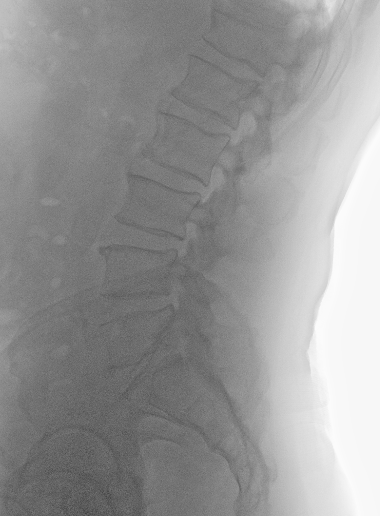

Las flechas rojas indican los niveles intervenidos. Obsérvese, comparando con niveles no intervenidos (flecha azul), la ausencia de ligamentos en espacio interespinoso e interlaminar

Postoperatorio

Los cambios postoperatorios son muy sutiles en la RM. Quizá en una RM dinámica (en bipedestación y extensión) pudieran apreciarse mejor.

En esta técnica hay que respetar la anatomía para no provocar una inestabilidad secundaria.